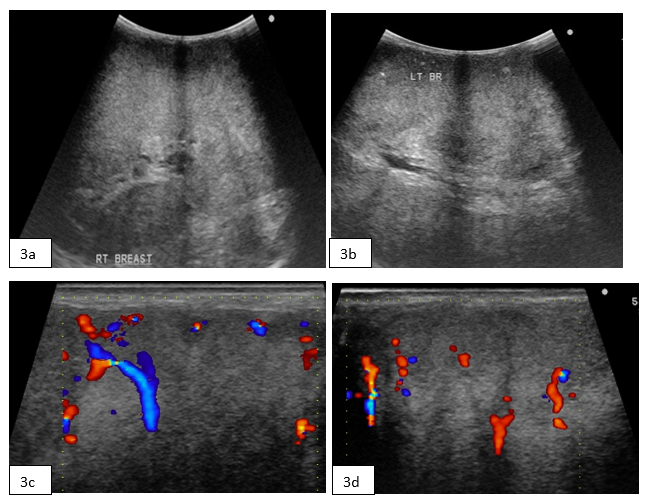

Fig 1a: Ultrasound shows coarse heterogenous liver parenchyma with surface irregularity & nodularity Fig 1b,c,d : CECT Imaging shows Small nodular cirrhotic liver with multi lobulated , well defined masses having mild heterogeneous post-contrast enhancement & few calcific foci in bilateral axilla and inguinal region. Hugely enlarged breasts partly seen in the scan. Ascites present. Fig 2 : 2D mammo (a,b) and Tomo images (c,d) of both breasts show bilateral high density large masses with smooth margins and no architectural distortion however few course heterogenous calcifications present randomly in breast parenchyma. (compromised scan quality is attributed to massive breast size) Fig 3 a,b,c,d : Ultrasound of bilateral breasts show iso to heteroechoic large breast masses occupying almost entire breasts. Normal breast tissue was compressed and difficult to identify. Colour doppler demonstrates significant vascularity within the masses. Fig 4 : Ultrasound of axillary lymph nodes. Fig 5 a,b : Biopsy from breast masses showed amyloid deposits (pink) predominantly around the ducts and blood vessels (a), demonstrated well on congo red stain (b).